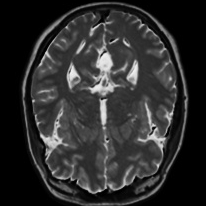

4.4 Qualitative Evaluation

In Figure 5 we analyze the prediction quality of our and compared approaches in a qualitative way. Considering modality propagation in MRI, we see that usage of uncertainty-aware patch invariance (UAPI) gives a better detailed weighting of the cerebrospinal fluid in the middle of the brain. In general, employing patch invariance yields better preservation of fine structures. This observation also applies to accelerated MRI enhancement. In particular, CUT and UAPI provide comparatively sharper knee images with more high-frequency details than the other methods.